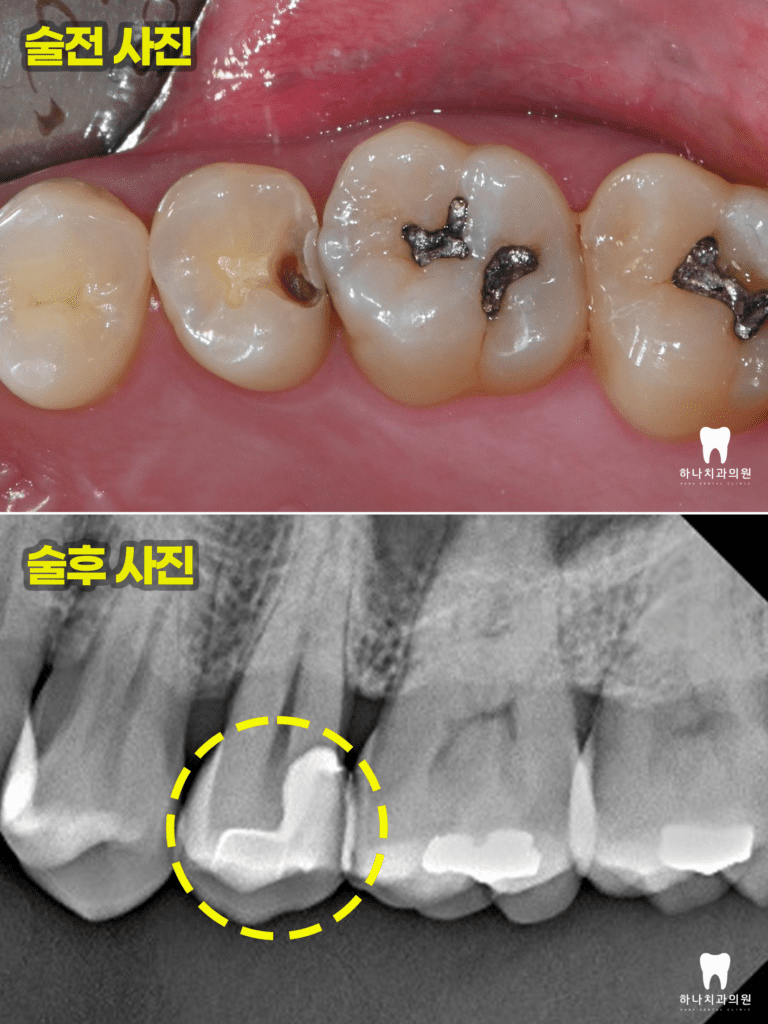

접근성과 방습에서 매우 어려운

왼쪽 아래 어금니의 치료 과정인데요.

이렇듯 수평으로 매복된 사랑니가

앞쪽 치아의 뒷면에 심한 우식을 발생시켜

발치로 이어지는 경우를 수없이 관찰합니다.

시간이 지체되어 가장 안쪽 어금니의

뒷면에 우식이 발생한 경우

치료가 매우 까다로울 수밖에 없는데요.

우석 우식 부위가 잇몸보다 아래에 위치하고

대부분 처치해야 할 부위가 잇몸뼈의 레벨보다

하방인 경우가 많아 직접적으로 처치하는 것이

수분의 컨트롤과 시야 확보, 기구의 접근성 등에서

거의 불가능에 가깝습니다.